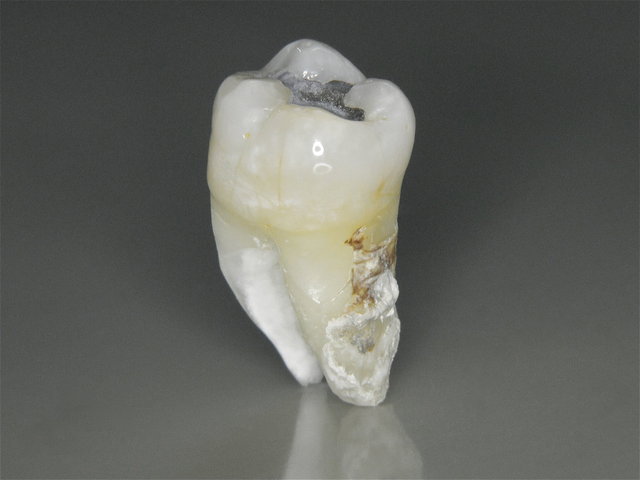

Tiefe Karies wegen eines benachbarten Weisheitszahnes

Tiefe Karies wegen eines benachbarten Weisheitszahnes ...

Composit-Füllung by CLINICDENT ✓

Extrahierter Stockzahn mit Zahnstein ...